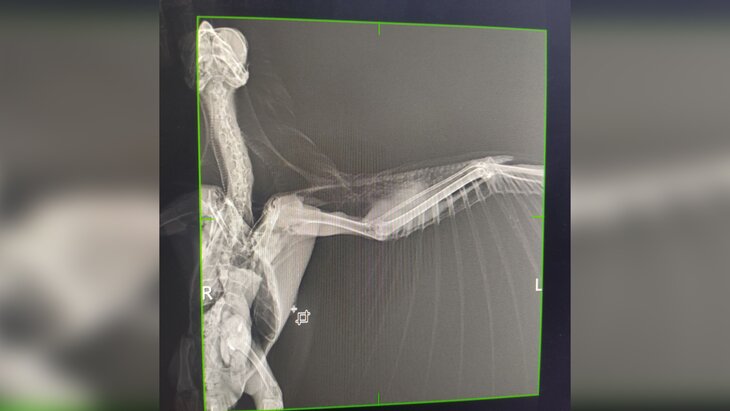

Фото: телеграм-канал "ЦРДЖ Пин и Пуф"

Ворона, которую спасли после того, как она, запутавшись в леске, провисела четыре дня на дереве в Уфе, скончалась в ветеринарной клинике. Об этом сообщается в телеграм-канале центра реабилитации диких животных "Пин и Пуф".

Птицу обнаружили на территории санатория "Зеленая роща". Зоологи, спасшие ворону, выявили у нее несколько травм. Руководитель центра Дмитрий Стрельников сообщал, что есть вероятность развития гематомы, опасной для жизни.

"Ушла на радугу. Оторвался тромб", – говорится в сообщении.